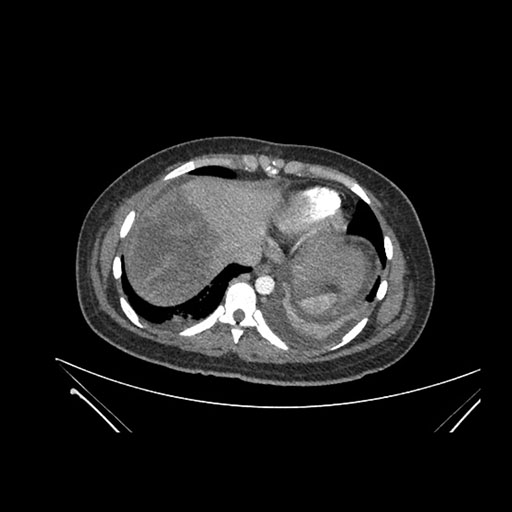

Axial Arterial

Axial Venous

Imaging analysis

Based on initial findings, which issue(s) would you be most concerned about?